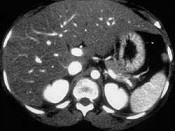

男,56岁,体型肥胖,有饮酒史30余年,CT检查见图,最可能的诊断是 ( )A、肝癌B、肝豆状核变性C、肝色素沉着症D、肝硬化E、脂肪肝

问题 男,56岁,体型肥胖,有饮酒史30余年,CT检查见图,最可能的诊断是 ( )

选项 A、肝癌 B、肝豆状核变性 C、肝色素沉着症 D、肝硬化 E、脂肪肝

答案 E